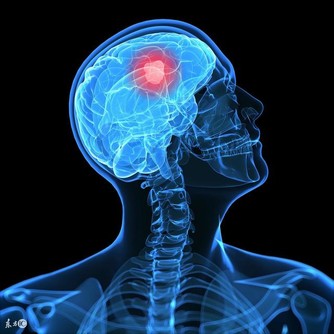

■懶事一:懶得學習,思維遲鈍。

△健康影響:機體衰老首先是從大腦開始,而多用腦可以延緩大腦衰老。

有些人過了50歲,心理上就開始懶惰,拒絕嘗試新事物,總是把「我懶得想」、「太複雜了」、「學不會」之類的話掛在嘴邊。然而,長期不願學習,久而久之會使腦功能會出現退行性改變,思維、記憶、分析、判斷等能力逐漸遲鈍。△調節方法:人都是傾向於做自己擅長或喜歡的事,所以,大家不妨從自己感興趣的事情開始學習,比如跳舞、下棋、養鳥等,活到老學到老。